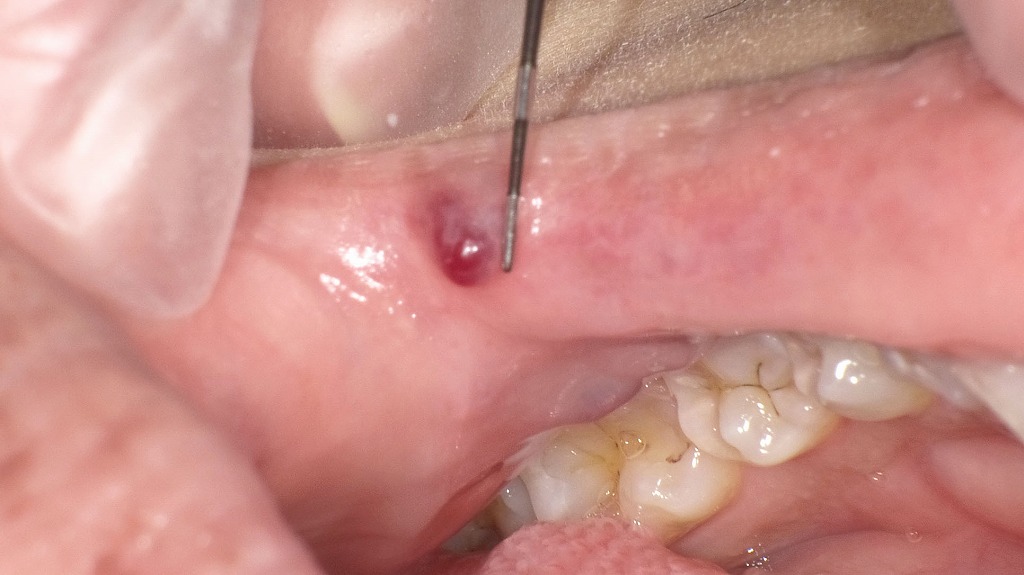

舌の点状出血(外傷性内出血)

舌の側縁部に赤紫色の点状変化が認められます。紫〜赤紫色で点在している所見は

毛細血管の破綻による内出血と一致します。

これは、舌を噛む・歯に接触するなどの**物理的刺激によって毛細血管が破綻し、内出血を起こした状態(舌の点状出血)**です。

潰瘍や硬結はなく、悪性所見は認められません。多くの場合、数日〜1週間程度で自然に改善します。